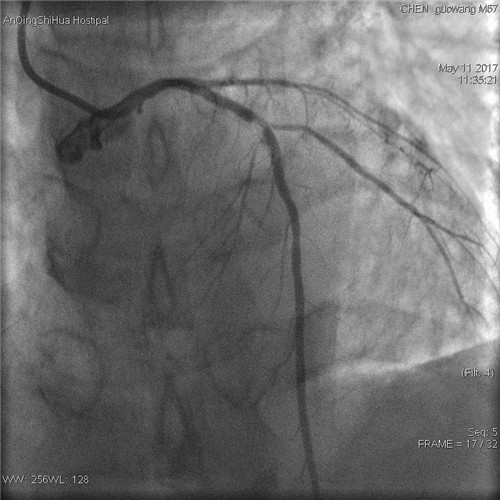

術(shù)前 前降支支架內(nèi)80%局限性再狹窄

該患者5年前曾因急性心肌梗死在外院行急診PCI治療(經(jīng)皮冠狀動(dòng)脈介入治療),于前降支植入支架一枚。此次由于活動(dòng)后突發(fā)胸悶,緊急入院,心血管內(nèi)科為其行冠脈造影檢查,提示前降支支架內(nèi)80%局限性再狹窄,回旋支完全閉塞,右冠向回旋支遠(yuǎn)端供應(yīng)側(cè)支,考慮為慢性閉塞。